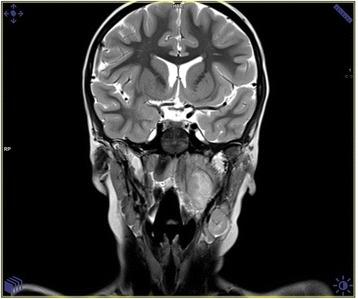

We present the analysis of 22 immunocompetent children treated with the clinical diagnosis of CSD in our hospital. Their ages were 2 to 16 years (mean 9.15 ± 2.2 years). Four of them presented classical papulas at admission time. Asymmetric, local lymphadenopathy was present in 16 patients. Five children, who presented an untypical course of CSD mimicking the oncological process, were analysed carefully. There were 3 patients with skull osteomyelitis, 1 with inflammation of the parotid gland, and 1 with an extra peripharyngeal mass. The diagnosis in these children was based on epidemiological, radiological, serological, and histological factors.

About 25 % of children with bartonellosis present an untypical spectrum of symptoms, including the lack of documented cat contact, primary lesions, or peripheral lymphadenopathy. Radiological methods like USG, CT, MRI present the unspecific masses, but they are not enough to distinguish the Bartonella inflammatory and oncological process. The final diagnosis was based on a histological method with additional polymerase chain reaction test.